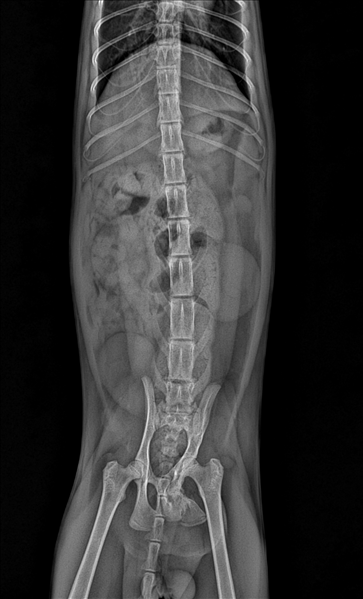

8개월 남아 코숏

최근 입양한 길냥이가 며칠간 대변을 못봐 진료를 봤습니다.

엑스레이 상 골반골절 의심 진단을 받고​​​​​​

현재 글과 첨부해주신 글만으로는 수술 가능 여부를 판단하기가 매우 어렵습니다. 특히 엑스레이상 이미 유합이 진행된(회복된) 상태로 보여 수술을 하게 된다면 의도적으로 재골절을 만들어 정렬을 다시 잡아야 하기 때문에, 이 경우 단순 골절 수술과는 난이도와 위험도에 차이가 납니다.

수술 가능 여부를 결정하려면 정밀 평가를 진행해 유합 상태와 변위 정도, 협착 정도, 신경/연부조직 평가, 직장 내가 평가도 해봐야 알 수 있습니다. CT 검사, 직장 조영 검사 등이 가능한 동물병원에 내원하셔서 상담을 받아보시는 것을 추천드립니다.